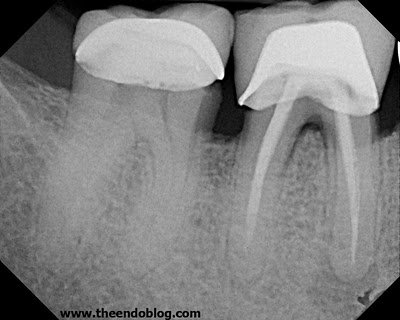

Retreatment completed in 2006.

In 2010, the patient returns with symptoms. The distal lesion has healed, and the mesial margin of the crown shows leakage. It is recommended to remove crown and excavate decay.